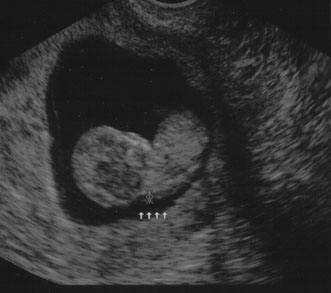

First trimester ultrasound may be performed transabdominally or transvaginally. Table 7 lists the components of a first trimester ultrasound. A crown–rump length, done between 7 and 13 weeks, can define a gestational age to within 5 days (Fig. 7).

Fig. 7. First trimester ultrasound showing crown–rump length.

Nuchal edema is an echo-free space between the skin line and the soft tissue overlying the cervical spine. Nuchal edema is caused by subcutaneous accumulation of fluid and has diverse etiology, including aneuploidies, cardiovascular and pulmonary defects, skeletal dysplasias, congenital infections, and hematologic and metabolic disorders. A nuchal translucency (NT) is obtained between 10 and 13 weeks' 6 days' gestational age (Fig. 8).31 A study at King's College Hospital in London found an NT of 3 mm was associated with a 4-times increase in the maternal age related risk for aneuploidy. An NT greater than 4 mm resulted in a 29 times increased risk for trisomies 21, 18, and 13. Additionally, with a 4 mm or more NT, there was a high incidence of other anomalies and poor prognosis, whereas with just 3 mm and a normal karyotype, the outcome was usually normal. Table 8 lists the disorders associated with an increased nuchal translucency thickness.

Fig. 8. Normal nuchal translucency of 0.19 cm at 11 weeks' gestation.